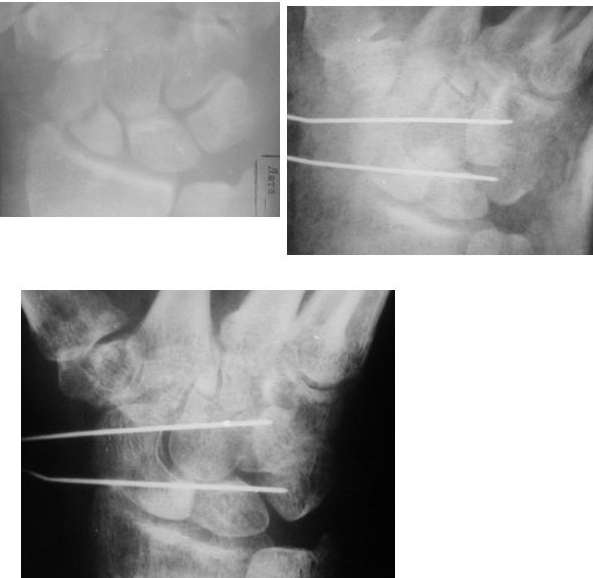

Ув. Данил! По моему мнению все-таки ложный сустав -склероз отломков (приложение), 5 мес, диастаз. Для подтверждения можно выполнить КТ кистевого сустава (формирование замыкательной пластинки, склероз концов отломков и т.д.,), а так же по КТ можно выявить сохраняется ли подвывих каких-либо костей запястья или нет. При наличии ложного сустава целесообразно будет удалить винт,обработать концы отломков, разрушив замыкательные пластинки и выполнить остеосинтез ладьевидной кости винтом с костной аутопластикой зоны псевдоартроза (либо гидроксиаппатитом...) Гипс 1,5 мес мин. Снимков найти сейчас не получилось. позже дошлю.